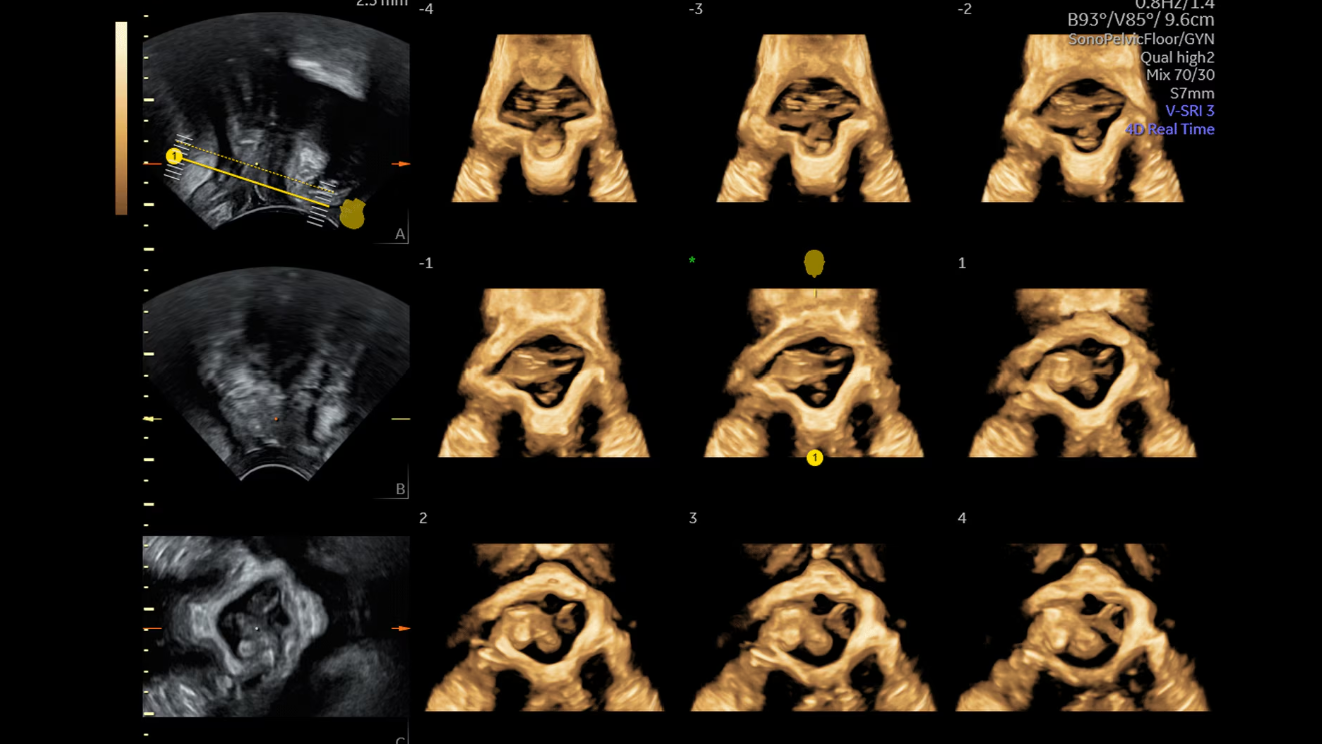

Серийные плоскости анатомии тазового дна, продемонстрированные с помощью SonoPelvicFloor, управляемого искусственным интеллектом